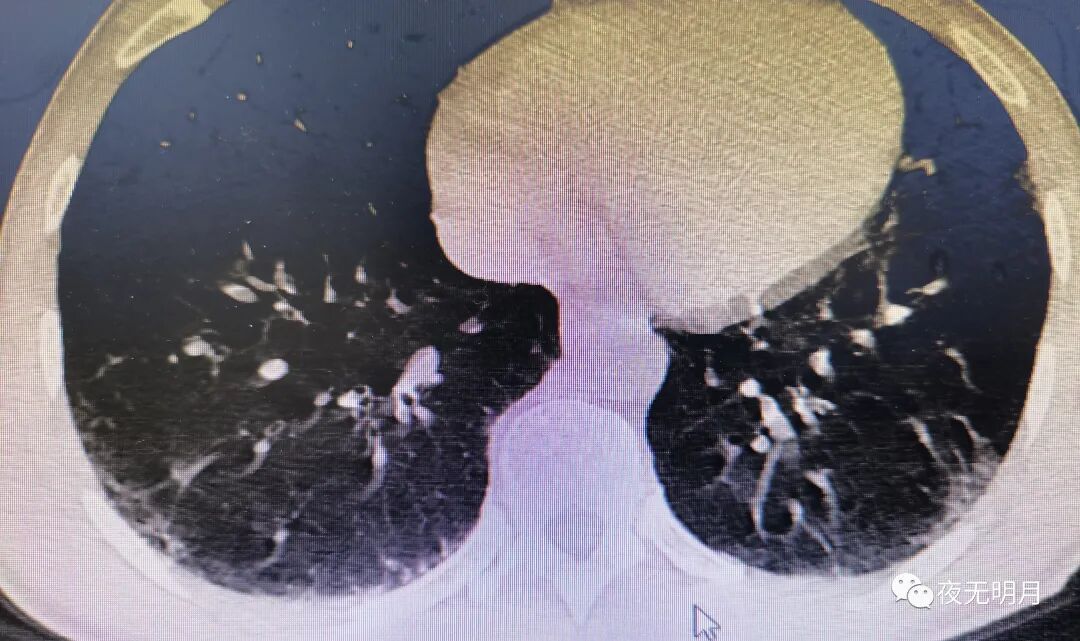

入院胸部CT:1、多发蜂窝影及网格影,考虑肺间质性纤维化改变,请治疗后复查。2、纵隔内多发肿大淋巴结。颈椎CT结论:C2/3、3/4、4/5、5/6、6/7颈椎退行性改变;C3-4椎间隙变窄。

西医诊断:1、肺间质纤维化;2、社区获得性肺炎 非重症。